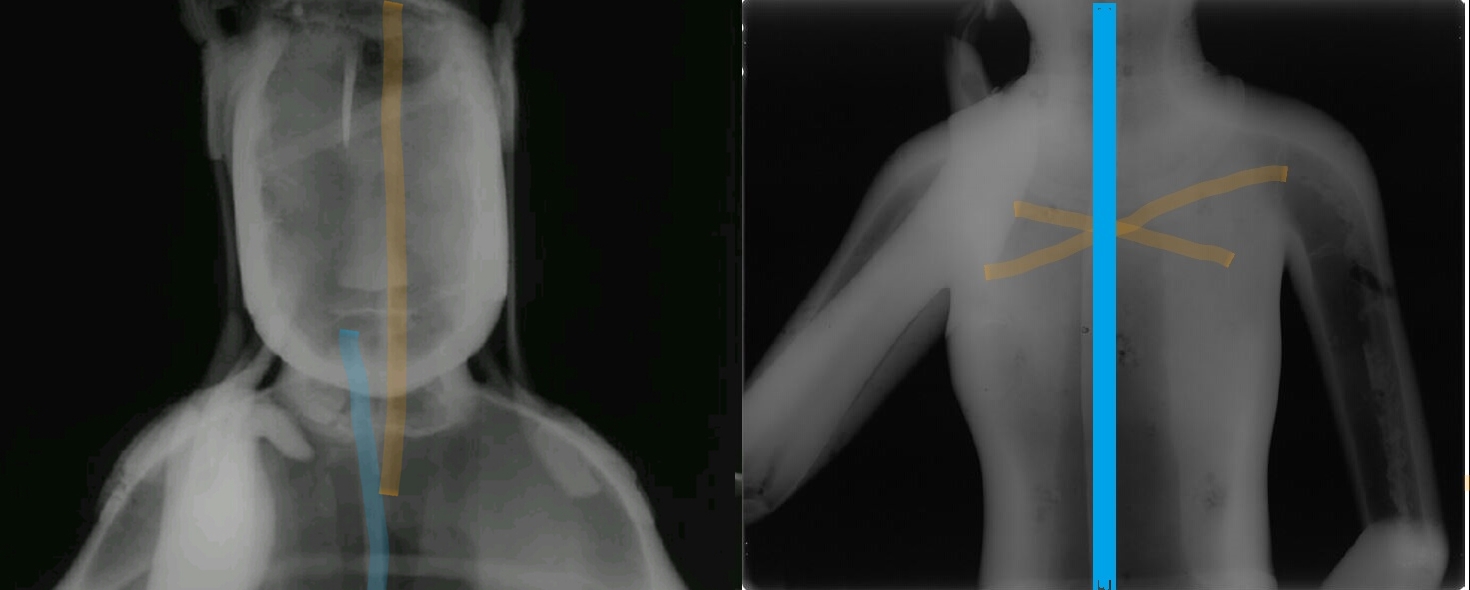

감마선 촬영 결과 78호의 경우 등 부위, 즉 목걸이와 늘어진 U자형 천의(보살 등이 입는 얇은 옷) 사이에 반타원형 동판을 따로 붙인 흔적을 확인했다. 주조할 때 생긴 구멍을 동판으로 붙여 수리한 흔적이었다. 지금까지 육안으로 관찰되지 않았던 수리흔적이 첨단과학을 동원하고 나서야 겨우 드러난 것이다.

그런데 78호를 감마선으로 분석해봤더니 철심틀이 분리되어 있었다.

이것은 점토(내형토)로 맨처음 형상을 만들 때 몸체와 머리 부분을 각각 따로 만들어 붙였다는 뜻이다. 왼발의 연화좌(불상이 앉는 자리) 역시 따로 제작해서 붙였다.

이렇게 별도로 만들어 붙였기 때문에 미세한 균열이 생겼고, 그 사이에 청동 쇳물이 흘러들어가 거스러미(까칠까칠한 부분)이 생겼다. 하지만 이 또한 육안이나 X선 촬영으로는 잡아낼 수 없는 흠결이었다.

또 비파괴방법 등으로 성분을 분석해보니 78호의 본체는 주석이 5% 정도 들어간 ‘구리-주석’ 합금이었다. 그런데 뒷면에 덧댄 동판과 수리흔적이 보이는 양 옆구리 부분에서는 주석 대신 납이 3% 정도 들어있는 구리-납 합금 성분이 보였다. 또 본체와 떨어져 있는 천의 자락과 보관 장식 중 일부도 구리-납의 합금이었다. 무슨 뜻일까. 주조가 한번이 아니라 몇번에 걸쳐 이뤄졌다는 것을 의미한다.

즉 처음 주조(구리-주석 합금) 때 쇳물이 제대로 흘러 들어가지 않아서 결함이 발생한 부분도 있었을 것이다. 또한 본체와는 떨어져있는 천의 부분은 처음부터 쇳물이 흘러 들어가지 못했을 것이다. 이런 부분을 ‘구리-납’의 합금 쇳물로 다시 주조했거나 혹은 별도의 납땜질 수리로 감쪽같이 마무리 한 것이다. 물론 이 역시 육안 또는 X선 촬영으로는 볼 수 없었던 흠결이었다.

정리하자면 78호 제작 때 등의 한가운데와 허리, 의자 뒤쪽의 윗부분, 몸체의 정수리 부분, 그리고 몸체와 떨어져있는 천의와 보발, 보관의 끝부분 등은 쇳물이 제대로 흘러가지 않아 결함이 생겼다는 뜻이다. 당시 분석에 참여한 민병찬 관장은 “78호의 이런 결함들을 구리 순도가 높은 구리-납 합금의 쇳물로 수리했다”면서 “일부는 결함 부분에 직접 쇳물을 부어 처리했거나 일부는 별도로 주조해서 붙였을 것”이라고 해석했다.